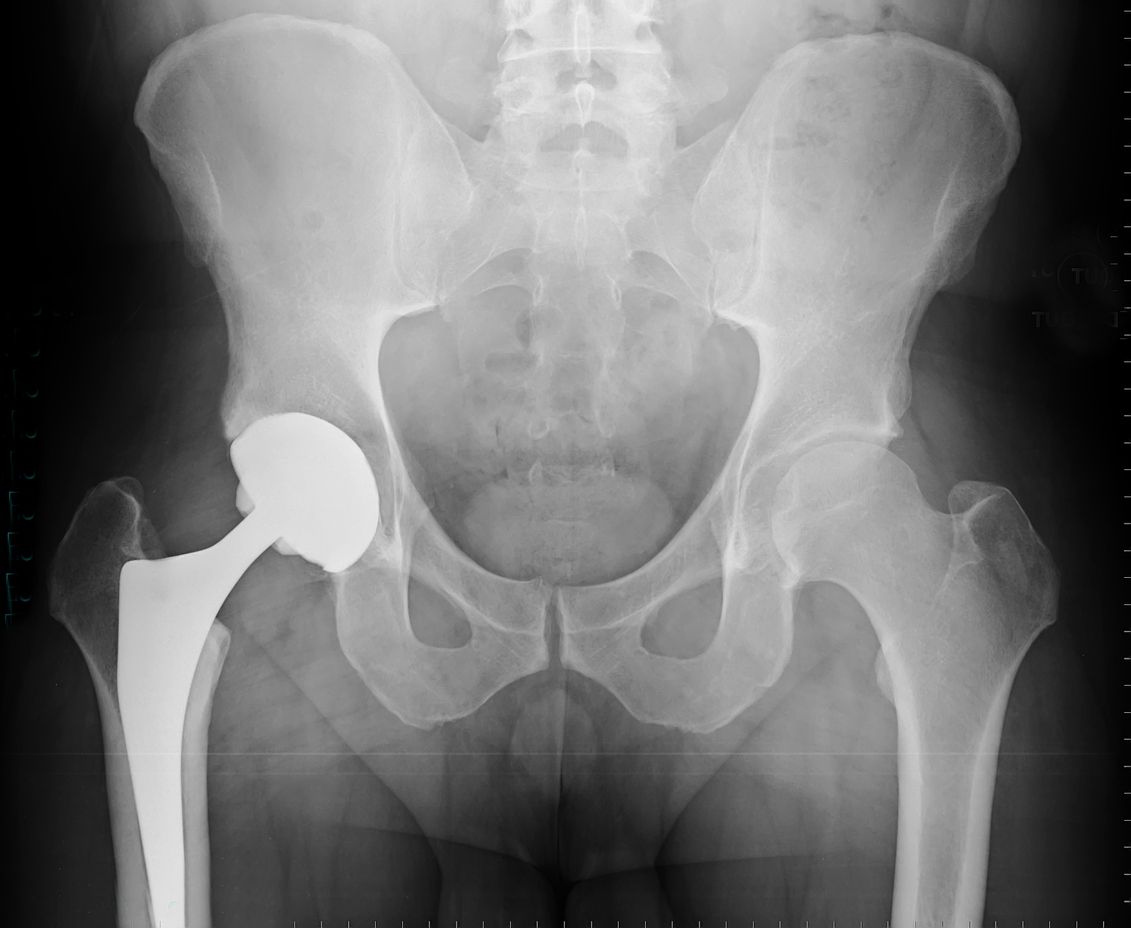

Von 2009 bis 2017 wurden Kobalt-Chrom-Implantate in Großbritannien transplantiert – insbesondere bei jüngeren Patienten, von denen angenommen wurde, dass sie am meisten davon profitieren würden. Diese Implantate wurden bei ihrer Markteinführung als innovativ angepriesen, da sie flexibler als herkömmliche künstliche Gelenke seien und mehr vom ursprünglichen gesunden Gewebe des Patienten erhalten blieben. Später stellte sich jedoch heraus, dass sich diese Implantate, die Kobaltbestandteile enthielten, zersetzen konnten, wodurch winzige Metallfragmente in den Blutkreislauf gelangen konnten und eine Reihe potenzieller Gesundheitsprobleme verursachen können. Eine Kobaltvergiftung wird mit Gedächtnisverlust, Depressionen, Seh- und Hörproblemen sowie Herzversagen und Nervenschäden in Verbindung gebracht.

Genau das passierte der ehemaligen Fitnesstrainerin Tracey O'Neill. Gegenüber The Telegraph machte sie nun öffentlich, wie sich das Hüftimplantat auf ihre Gesundheit ausgewirkt hat. Sie hatte gehofft, der Eingriff würde ihr helfen, ihre Beweglichkeit wiederzuerlangen, als sie sich 46-jährig im Jahr 2014 zum ersten Mal einer Hüft-OP unterzog. Stattdessen litt sie jahrelang unter gesundheitlichen Problemen, die ihr das Gefühl gaben, "im Körper einer 90-Jährigen gefangen" zu sein, und irgendwann begannen die Leute an ihrem Geisteszustand zu zweifeln.

O'Neill, der 2015 ein zweites ähnliches Implantat in die Hüfte eingesetzt wurde, bemerkte zunächst allgemeine Schmerzen und eine Schwellung rund um das Gelenk. Im Jahr 2019 litt sie unter Kurzatmigkeit und Müdigkeit sowie Herzproblemen. "Ich kam an den Punkt, an dem ich es nicht einmal mehr in einer einfachen Yogastunde schaffte, mich auf den Boden zu setzen und wieder aufzustehen", sagte sie gegenüber The Telegraph. "Manchmal redete ich mit Leuten und vergaß einfach das nächste Wort. Die Leute dachten, ich hätte den Verstand verloren."

Obwohl sie seit Jahren unter den Beschwerden litt und der britische Gesundheitsdienst NHS den allgemeinen Einsatz dieser Implantate 2017 einstellte, nachdem die Risiken deutlich wurden, dauerte es bis zum Jahr 2020, bis Mediziner den Zusammenhang zwischen ihren Symptomen und dem künstlichen Gelenk herstellten. Bei der heute 56-Jährigen wurde das erste Implantat operativ entfernt und durch ein Implantat aus einem anderen Material ersetzt. Beim zweiten Implantat wird derzeit auf Anzeichen von Verschleiß geachtet.